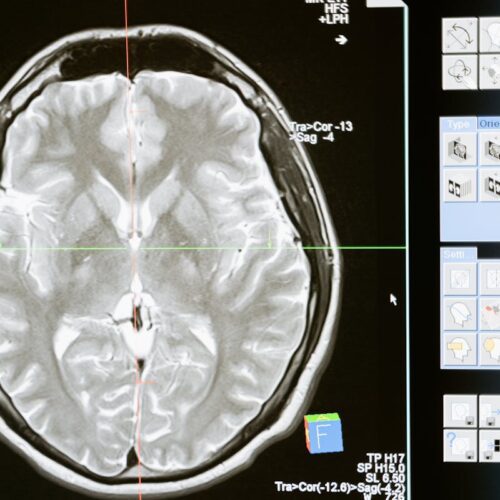

Aplicações DICOM e Desenvolvimento de Software: Do Viewer ao Código